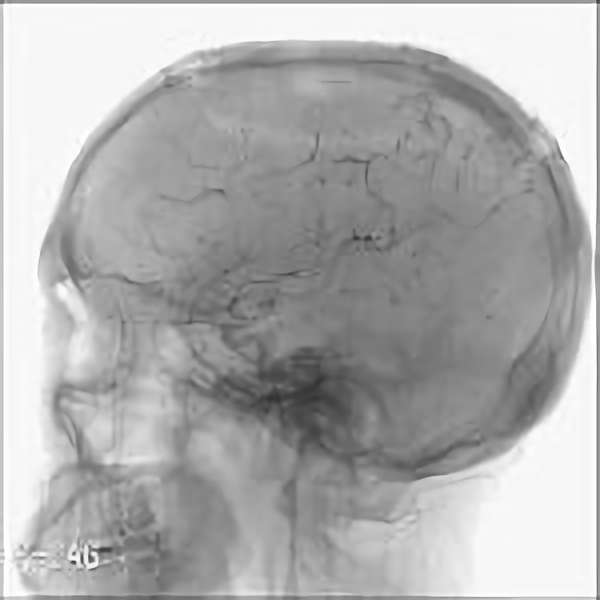

脳血管撮影

手術前